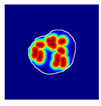

| True label: Endocapillary |  |  |  |  |  |

| single-multiclass: Endocapillary p = 1.000, IoU = 0.055 | |||||

| multiple-binary: Endocapillary p = 0.993, IoU = 0.029 | |||||

| spatially guided: Endocapillary p = 0.976, IoU = 0.710 | |||||